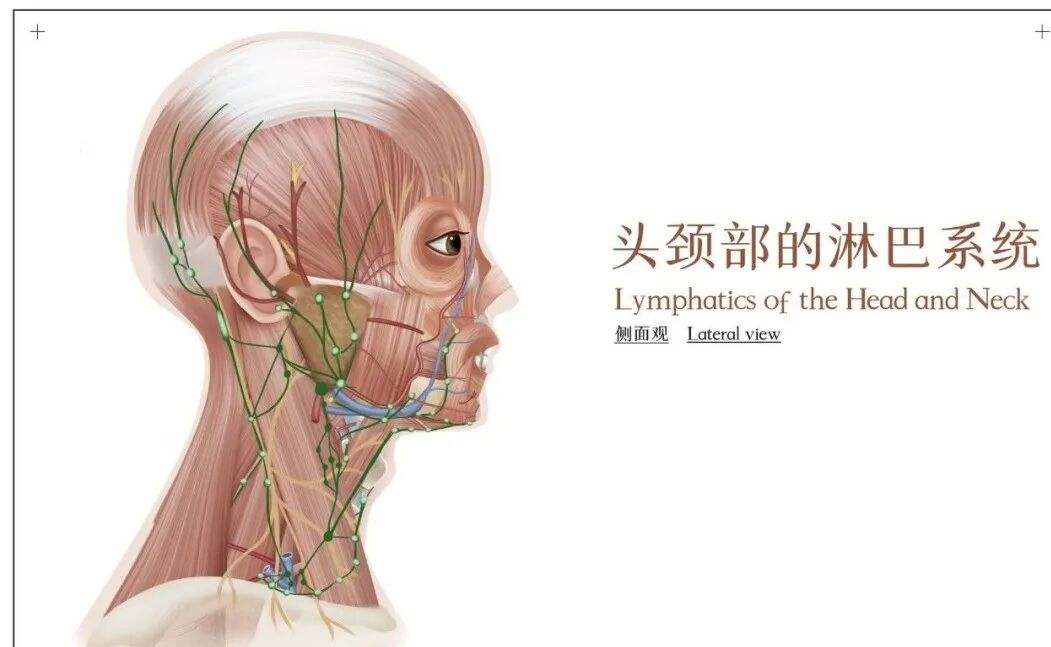

胸腺是机体的重要淋巴器官,其功能与免疫紧密相关,主要分泌胸腺激素及激素类物质,是具有内分泌机能的器官。胚胎后期及初生时,人胸腺约重10~15克,是一生中重量相对最大的时期。随年龄增长,胸腺继续发育,到青春期约30~40克。此后胸腺逐渐退化,淋巴细胞减少,脂肪组织增多,至老年仅15克。

胸腺位于心脏附近的胸骨柄后面,于胎儿时期最为活跃,以建立起身体的免疫系统,出生后分泌胸腺生成素来增强免疫系统。其基本功能是为每一个细胞打上能够辨识的记号,防止免疫细胞反抗并摧毁我们身体自己的细胞,使身体能够抵抗疾病的传染。

所以说,胸腺是主管着我们人体的免疫系统。如果胸腺功能下降了,人们就容易生病感冒。这时到医院里,医生就是建议经常感冒的人打一种药叫胸腺肽。但是一旦打了胸腺肽以后,人体自身的胸腺分泌就会更弱了。所以,人们又称胸腺为感冒的遥控器,容易感冒的人平时一定要注意胸腺的保养。

胸腺是机体的重要淋巴器官,其功能与免疫紧密相关,主要分泌胸腺激素及激素类物质,是具有内分泌机能的器官。胚胎后期及初生时,人胸腺约重10~15克,是一生中重量相对最大的时期。随年龄增长,胸腺继续发育,到青春期约30~40克。此后胸腺逐渐退化,淋巴细胞减少,脂肪组织增多,至老年仅15克。

胸腺位于心脏附近的胸骨柄后面,于胎儿时期最为活跃,以建立起身体的免疫系统,出生后分泌胸腺生成素来增强免疫系统。其基本功能是为每一个细胞打上能够辨识的记号,防止免疫细胞反抗并摧毁我们身体自己的细胞,使身体能够抵抗疾病的传染。

所以说,胸腺是主管着我们人体的免疫系统。如果胸腺功能下降了,人们就容易生病感冒。这时到医院里,医生就是建议经常感冒的人打一种药叫胸腺肽。但是一旦打了胸腺肽以后,人体自身的胸腺分泌就会更弱了。所以,人们又称胸腺为感冒的遥控器,容易感冒的人平时一定要注意胸腺的保养。